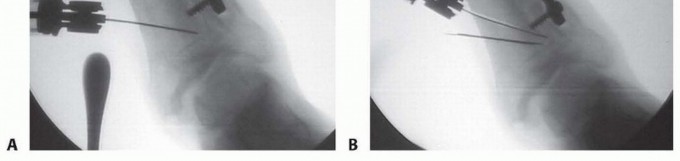

## For valgus deformities, a second osteotomy is made at an angle to the first corresponding to the amount of bone to be resected according to the preoperative plan. This is also done with a power saw, ending at the lateral extent of the first osteotomy, and the wedge is removed (TECH FIG 3A,B).

## TECH FIG 3 • A. AP intraoperative view of the ankle showing a Crego elevator in place with a saw blade performing the initial osteotomy. B. AP intraoperative view of the ankle with a saw blade placed into the initial cut and the saw completing the second cut.